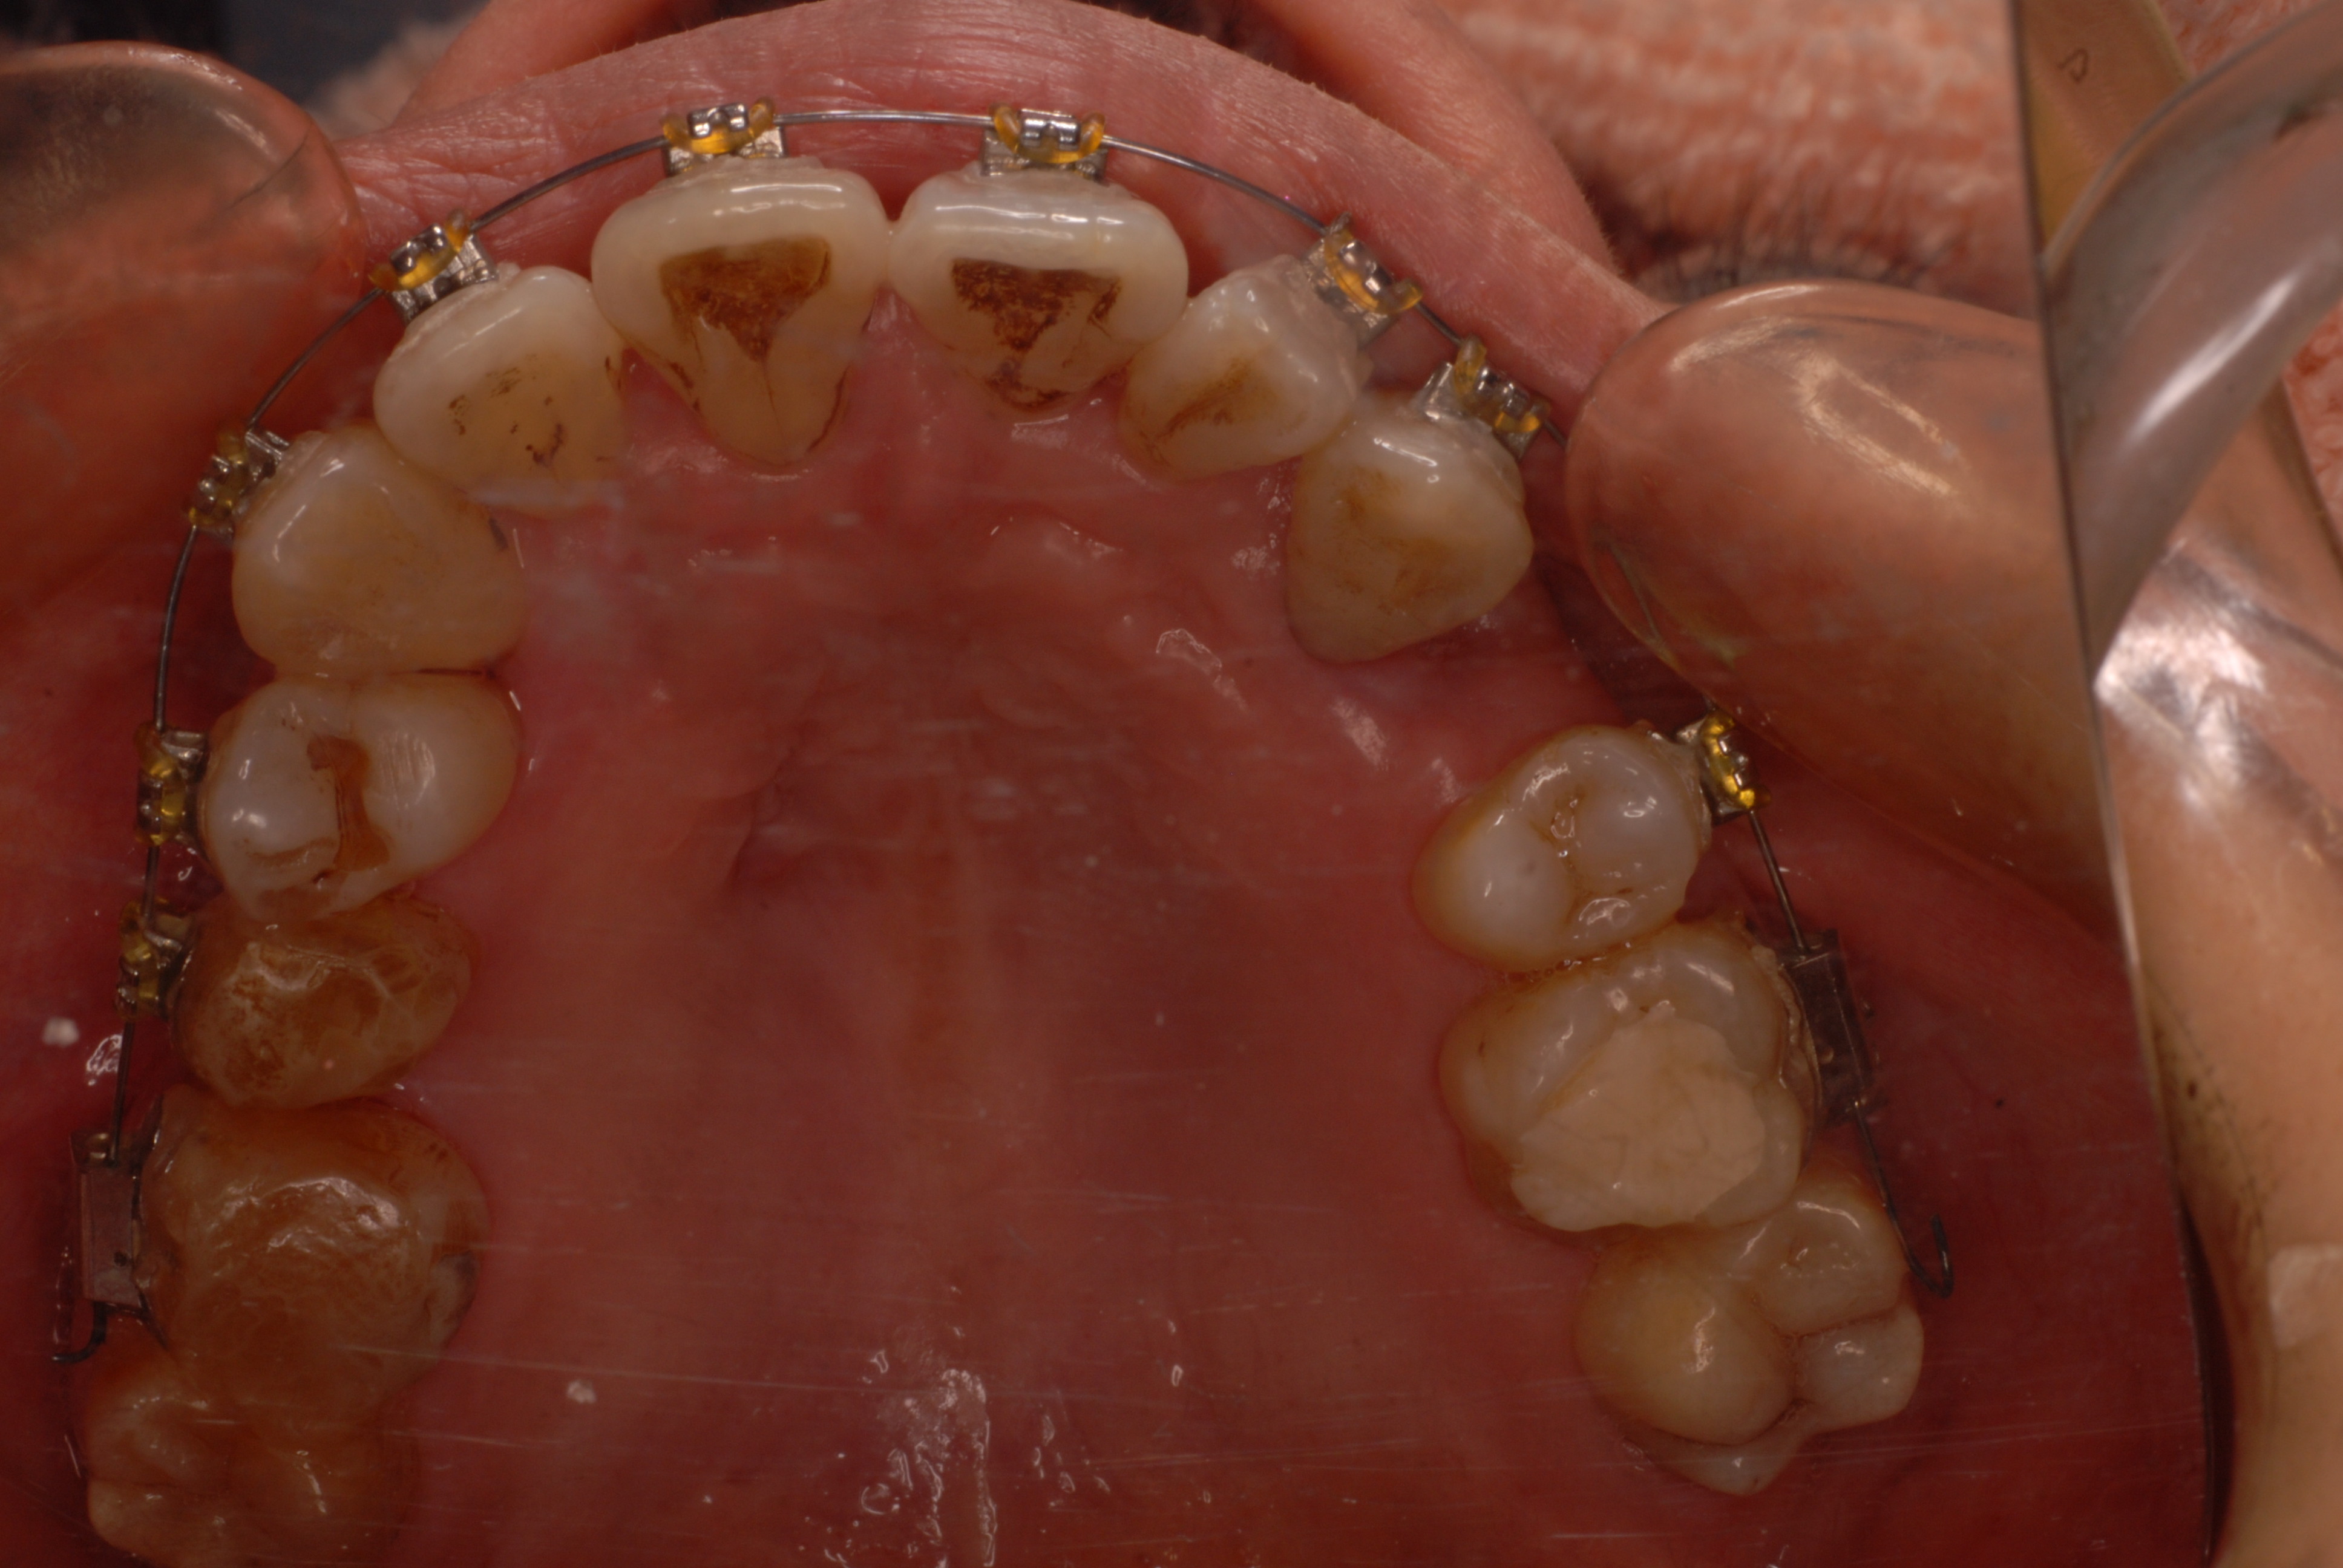

下の写真の方は虫歯と歯の間の歯周病が酷かったのです。

虫歯の治療も完全にできませんし、歯の位置が悪く又重なっている為に歯周病が治らずに説得に数カ月を有した後に矯正することになりました。

写真左の歯のうち過剰歯と糸きり歯の隣を抜きました。